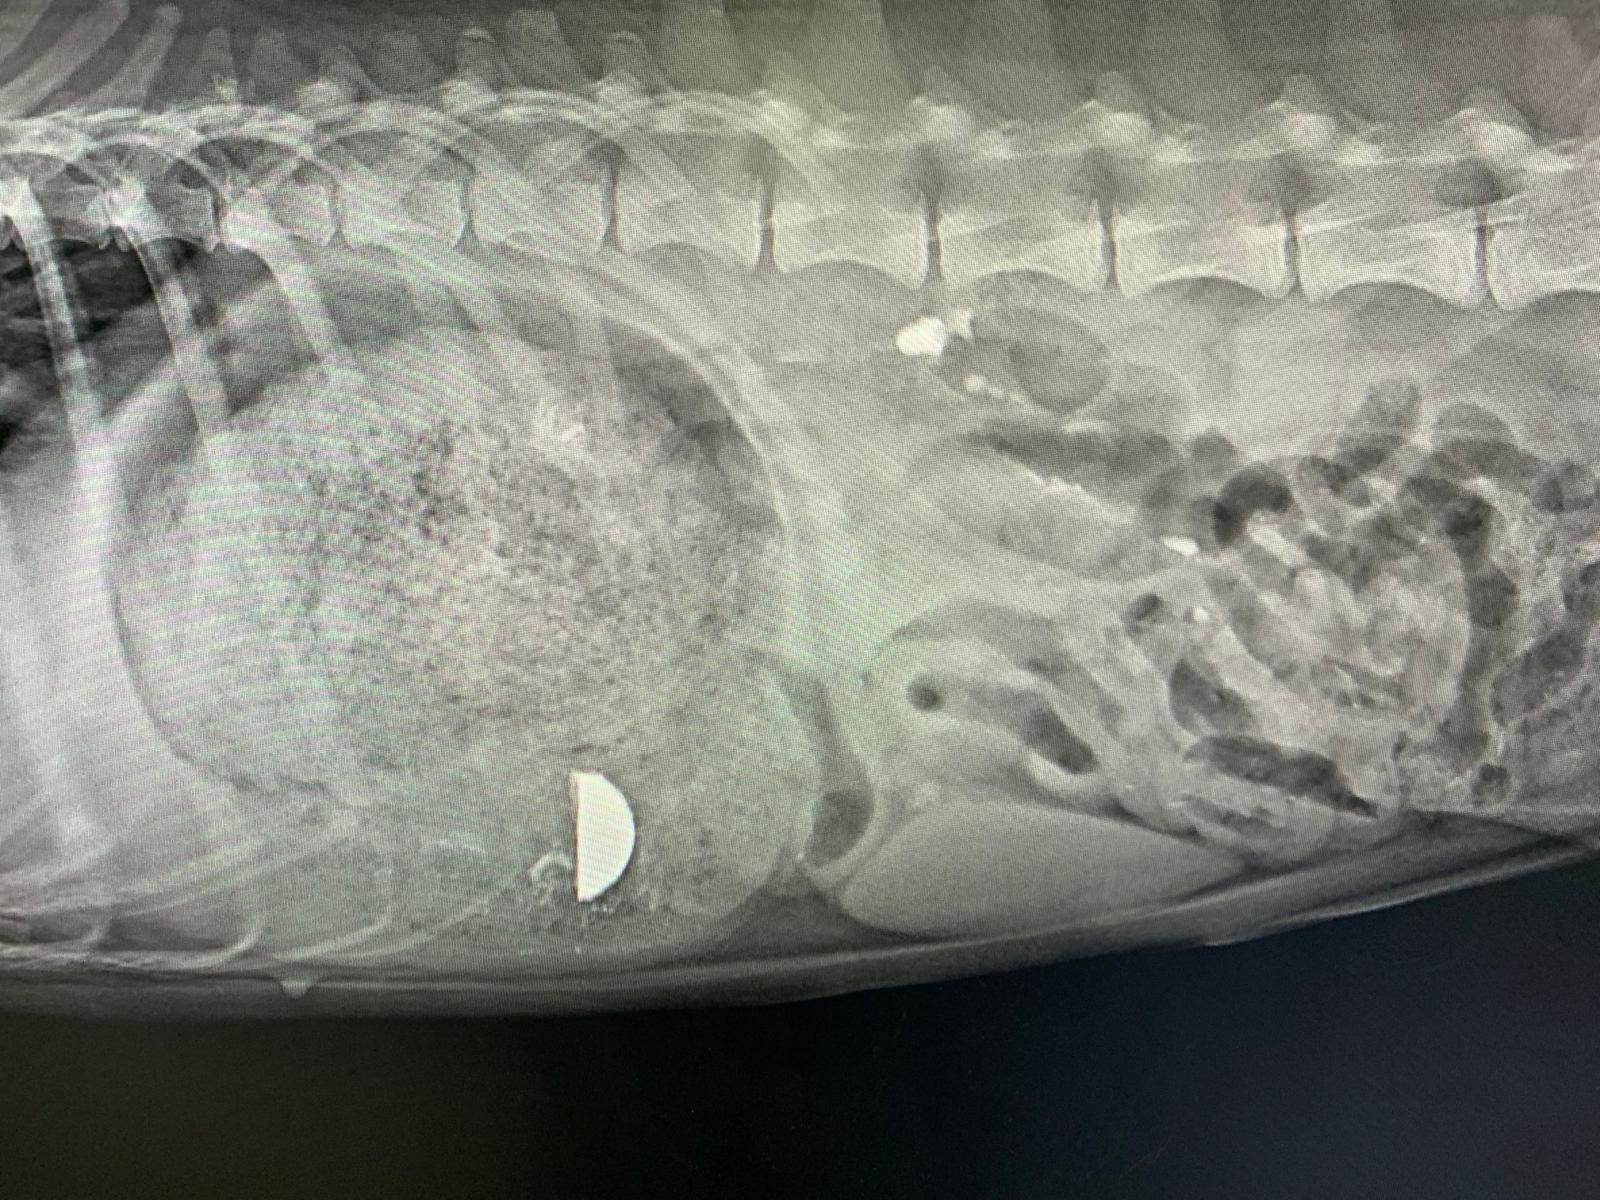

K9 Horse Club Veteriner Kliniği, evcil dostlarınızın doğru tanı ve tedavi süreçlerini desteklemek için kapsamlı DR röntgen hizmetleri sunmaktadır. Modern röntgen cihazlarımız ile kas, iskelet ve iç organ görüntülemeleri hızlı ve güvenli bir şekilde gerçekleştirilir. Alanında deneyimli veteriner hekimlerimiz, röntgen sonuçlarını profesyonel olarak değerlendirir ve tanıya uygun tedavi planları oluşturur. Hem köpekler hem de atlar için uygulanan röntgen hizmetimiz, doğru tanı koyma ve etkili müdahale sağlama açısından kritik bir rol oynar. K9 Horse Club, veterinerlik hizmetlerinde yüksek kalite ve güvenliği ön planda tutar.